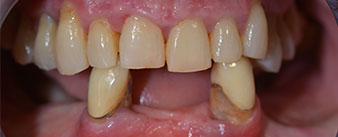

La paziente, 64 anni, presenta una dentatura residua di denti 38, 33 e 43 e una protesi combinata innestata nella mandibola (Fig. 1 e 2).

L'indispensabile trattamento parodontale e l'estrazione dalla mascella erano previsti per un altro periodo, perché la paziente è un'insegnante e all'epoca era molto impegnata con gli esami. Tuttavia, aveva difficoltà a parlare correttamente o a mangiare, perché la protesi momentanea era molto fragile e si rompeva alla minima sollecitazione.

Dopo aver illustrato alla paziente le varie opzioni di trattamento disponibili, la donna ha preferito scegliere l'estrazione della dentatura residua dalla mandibola, procedendo poi all'implantologia immediata e al trattamento con il metodo Fast & Fixed (Bredent medical). In questo caso, la protesi fissa provvisoria viene innestata su quattro impianti lo stesso giorno dell'intervento. L'obiettivo è quello di operare la paziente il venerdì, permettendole di essere presente agli esami orali il lunedì seguente.